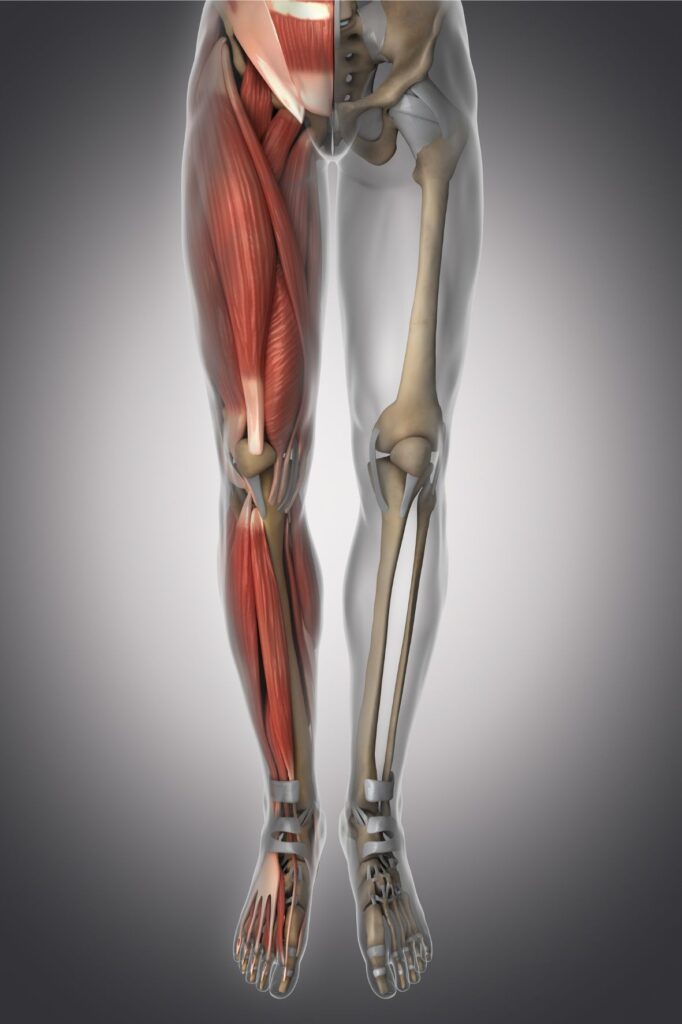

II. Anatomia nogi

A. Zrozumienie mięśni, kości i stawów

- Mięśnie: Noga składa się z wielu mięśni, które pełnią różnorodne funkcje. Mięśnie ud, łydki, uda przedniego i tylne, pośladkowe oraz stopy są zaangażowane w ruchy, stabilizację i podtrzymywanie ciała podczas chodzenia, biegania i wykonywania innych aktywności.

- Kości: Noga składa się z kilku głównych kości, w tym kości udowej, piszczelowej, strzałkowej, piętowej i kości śródstopia. Kości te są połączone stawami, które zapewniają ruchomość i stabilność.

- Stawy: Noga zawiera różne stawy, które umożliwiają ruchy zgięcia, wyprostu, obroty itp. Wszystkie stawy pracują w harmonii, umożliwiając nam poruszanie się w różnych kierunkach.

B. Jak anatomia nogi ma się do bólu

- Uszkodzenia mięśni: Przeciążenie, nadmierna aktywność fizyczna, niewłaściwa technika treningowa lub nagłe ruchy mogą prowadzić do mikrouszkodzeń mięśni. To może prowadzić do bólu mięśniowego, napięcia lub skurczów.

- Uszkodzenia kości: Złamania, stłuczenia, zwichnięcia i inne kontuzje kostne mogą prowadzić do silnego bólu nogi. Przykłady obejmują złamania kości, naderwania więzadeł lub naciągnięcie mięśni.

- Uszkodzenia stawów: Choroby stawów, takie jak zapalenie stawów, reumatoidalne zapalenie stawów lub dna moczanowa, mogą prowadzić do zapalenia i obrzęku stawów, co powoduje ból i ograniczenie ruchomości.

- Kompresja nerwów: Noga zawiera wiele nerwów, które są podatne na ucisk lub uszkodzenie. Uwięźnięcie lub uszkodzenie nerwu może prowadzić do bólu, mrowienia, drętwienia lub osłabienia mięśni wzdłuż trasy nerwu.

Anatomia nogi odgrywa kluczową rolę w pojawianiu się bólu. Zrozumienie struktury anatomicznej pomaga lekarzowi zidentyfikować przyczyny bólu i wdrożyć odpowiednie leczenie, takie jak rehabilitacja, leki przeciwbólowe, terapia fizyczna, zastrzyki lub interwencje chirurgiczne w niektórych przypadkach.